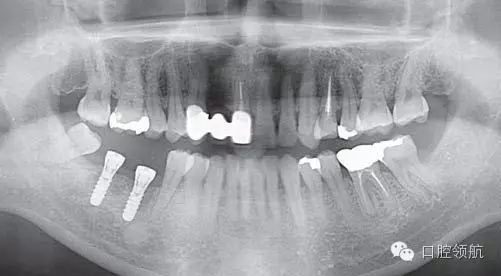

(右下第七、六顆牙)種植體植入術(shù)后(圖1),(右下第七、六顆牙) 拔牙后4個(gè)月植入種植體,埋入時(shí),使用動(dòng)度測(cè)量儀測(cè)量ISQ值為(左下第六顆牙):70∕70;(左下第七顆牙) :75∕75,顯示了良好的初期穩(wěn)定性,6周后又重新測(cè)定了ISQ值為: (左下第六顆牙) :70∕70;(左下第七顆牙):79∕79,遂取印模,制作上部結(jié)構(gòu)(圖2)。因?yàn)榭紤]需要2周的技工制作時(shí)間,所以計(jì)劃在埋入后2個(gè)月安裝最終的上部結(jié)構(gòu)修復(fù)體

圖1 種植體植入后的曲面斷層片。